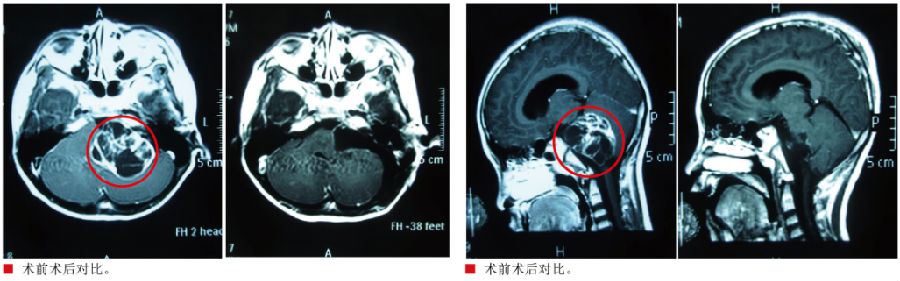

入院查体:患儿神志清醒,对答切题,遵嘱活动,双侧瞳孔等圆等大,直径约2.5mm,对光反射灵敏,视力、视野基本正常,左侧面部麻木感,左耳听力下降,左侧鼻唇沟变浅,嘴角向右歪斜,颈软,右侧肢体肌力Ⅴ级,左侧肢体肌力IV级,感觉、肌张力基本正常,生理反射存在,病理反射未引出,脑膜刺激征(-),闭目难立征阳性,小脑共济失调征(-)。我院头颅MR提示:左侧桥小脑角区占位性病变,大小约51mm×43mm×55mm,增强后囊壁及实性部分明显强化,左侧听神经根明显增粗强化,脑干、左侧桥壁及左侧小脑半球明显受压,考虑听神经瘤可能。

3月8日在全麻下行左侧桥小脑角区占位性病变切除术,取左侧乙状窦后入路,术中见肿瘤位于左侧桥小脑角,有完整包膜,质软,呈囊实性,血供偏少,边界清,电生理监测,显微镜下仔细分离,整块切除,中后组颅神经保留完整,肿瘤全切,电生理功能正常,术中出血约200ml,手术顺利结束。

术后患儿左侧面部麻木感消失,经专科治疗,左耳耳鸣及听力症状均较前好转,无后组颅神经损害症状,康复出院。病理提示:听神经鞘瘤。